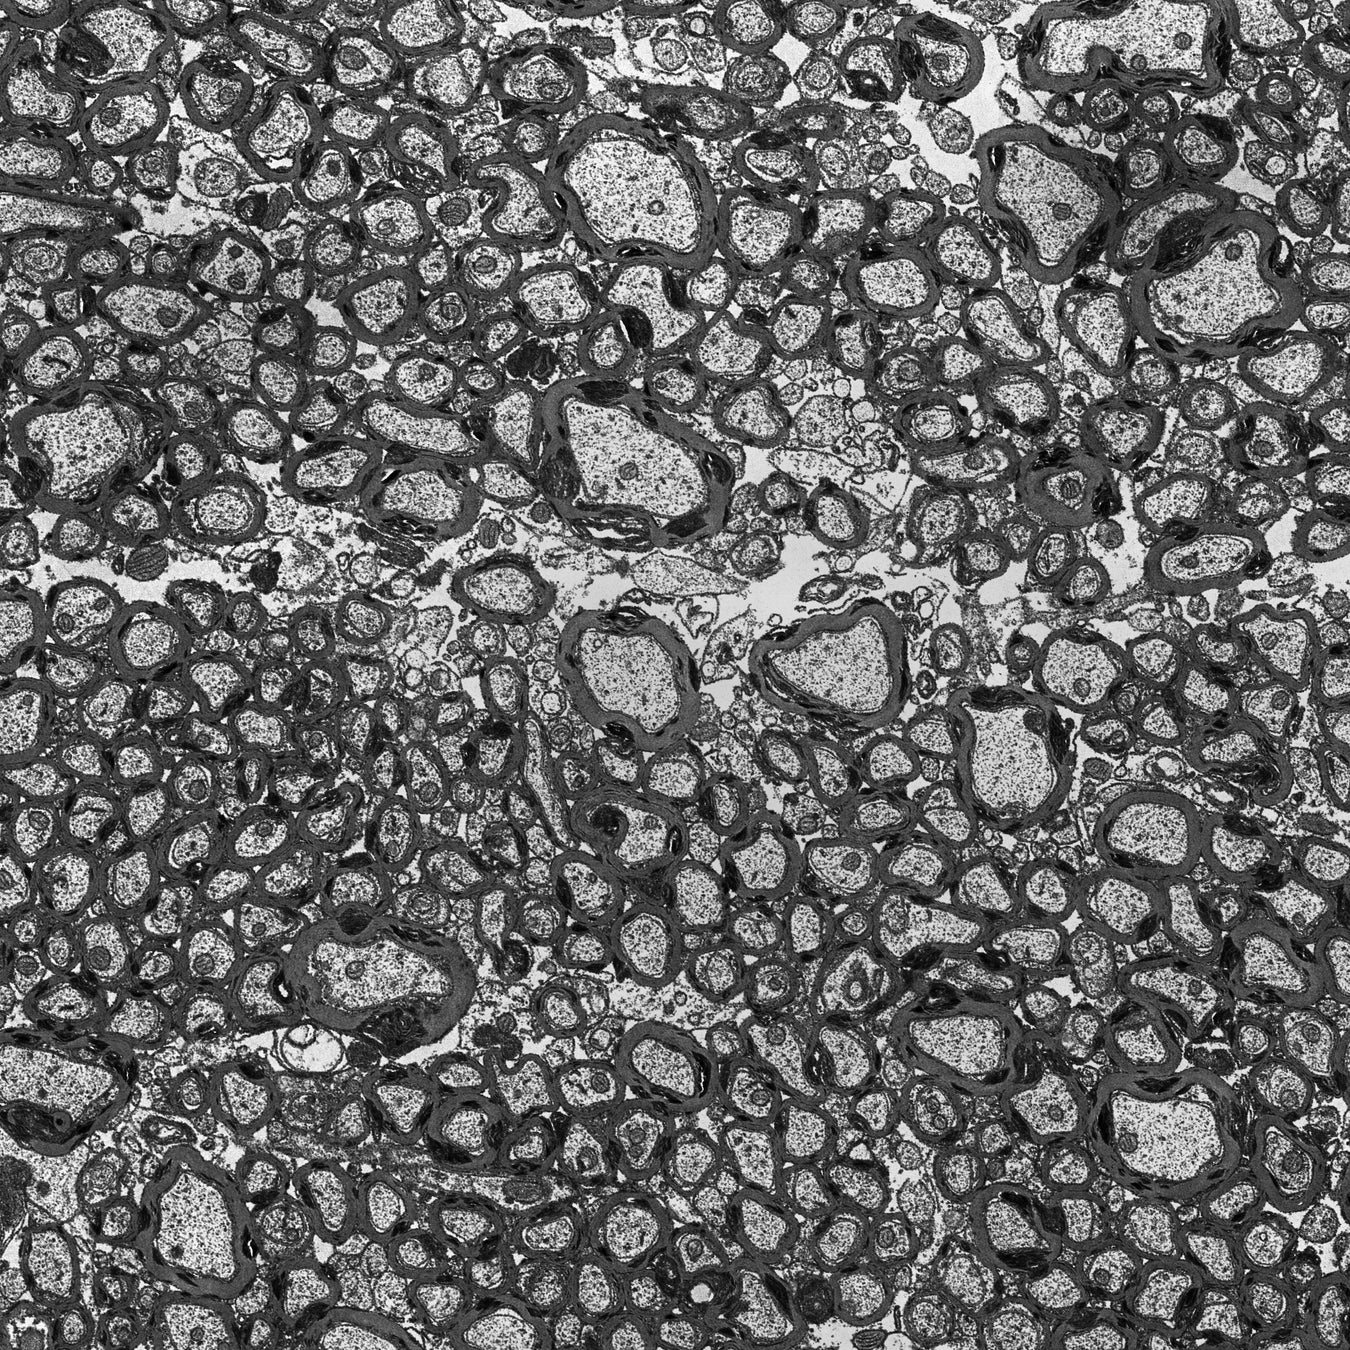

※ 「Blade™」が捉えたネズミの有髄神経繊維(プリンストン大学神経科学研究所 ジェン・ジハオ博士提供)

今回受賞した「Blade™」は、既存の透過型電子顕微鏡(TEM)にATUM(超薄連続切片自動回収機)を活用した超高スループット画像処理を付加するアクセサリで、従来のワークフローを100万倍のスピードに改善します。広域の視野を効率的にキャプチャし、被写体をフル解像度のモンタージュ画像としてスピーディに出力することができます。これまで手動で莫大な時間をかけて行われてきたサンプル前処理とイメージキャプチャのプロセスを完全自動化し、業界に抜本的な変革をもたらした点が評価されました。

「Blade™」以前、膨大な時間と労力をかけてエキスパートが得られるデータは、微量の細胞、材料、化学構造に限られていました。「Blade™」は、精密なサンプル供給と、高度なイメージ復元を超高速に完全自動で行います。これによって、ナノスケールの構造を大規模に観察し、大量データに基づいた調査が可能になりました。例えば、脳神経学において、従来の方法で脳組織や脳回路の完全な復元ができたのは、小さな昆虫やミミズのような単純な生物のみでした。現在は大型の昆虫、魚、小型哺乳類などより複雑な生物の脳回路や脳全体の復元が進んでいます。本製品は、米国プリンストン大学、アレン脳科学研究所、日本の生理学研究所、ドイツのシャリティ・ベルリン医科大学など、世界的にトップレベルの研究機関で上記のような研究に利用されています。